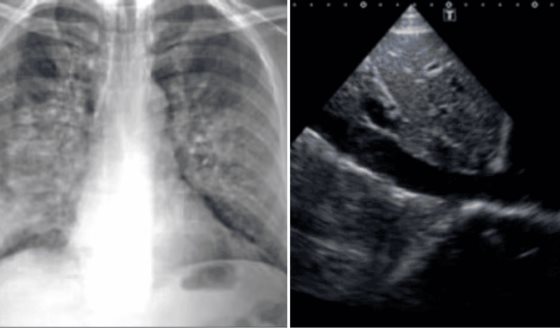

Por otro lado, el "síndrome del corazón festivo", o síndrome del corazón en "sábado por la noche", es una condición que ocurre como resultado del consumo excesivo de alcohol combinado con otros factores como trasnochos, estrés emocional o físico, y, en algunos casos, la ingesta de comidas copiosas.

Esto también es otro factor que puede provocar alteraciones en el ritmo cardíaco, como fibrilación auricular u otras arritmias, y está asociada con el aumento de la frecuencia cardíaca (taquicardia) y la disminución de la variabilidad de esta frecuencia.

De hecho, el término se originó al observar un incremento en los casos de arritmias cardíacas durante los fines de semana o períodos festivos, cuando es más común excederse en el consumo de alcohol, como navidad y año nuevo.